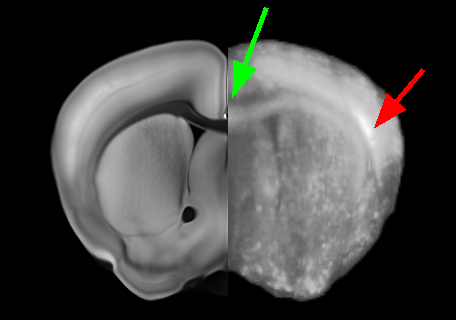

For registration, each CLARITY volume I0subscript𝐼0I_{0} was downloaded from the NeuroData cluster. They were resampled to a 50 μm𝜇𝑚\mu m resolution and registered to ARA atlas image J1subscript𝐽1J_{1} with 12-parameter affine alignment under MI matching. Deformable registration was then done with MI-LDDMM as implemented in ndreg. A cascaded-α𝛼\alpha approach was adopted in which a smoother registration with α=0.05𝛼0.05\alpha=0.05 was followed by registrations at α=0.02𝛼0.02\alpha=0.02 and α=0.01𝛼0.01\alpha=0.01 to refine the results (Fig. 2). Both ARA-aligned CLARITY volumes and CLARITY-aligned ARA annotations were uploaded to the NeuroData cluster. This allowed us to visualize ARA annotations overlaid on the terabyte-scale CLARITY images (Fig 1). Deformable registration was done with SSD-LDDMM and Mask-LDDMM to demonstrate the advantages of MI-LDDMM. For validation MI-LDDMM was also compared to SyN ANTs [1] with MI cost and σ=1.0𝜎1.0\sigma=1.0 mm Gaussian regularization (Fig. 3).

Refer to caption

(a) SSD- LDDMM

(b) Mask- LDDMM

(c) MI- LDDMM

(d) SyN

Figure 3: Comparison of SSD-LDDMM (3(a)), Mask-LDDMM (3(b)), MI-LDDMM (3(c)) and SyN ANTs (3(d)) registration of CLARITY volume. Panes (3(a)-3(d)) have an ARA coronal slice on the left juxtaposed to the corresponding aligned CLARITY slice on the right. Green arrows point out that the corpus callosum is misaligned by SSD-LDDMM but aligned correctly by MI matching. Red arrows show that SSD-LDDMM distorts bright regions. Fiducial landmarks were manually placed in the corpus callosum, and midbrain of the acquired volumes. Pane (3(e)) compares mean errors between the deformed CLARITY and ARA landmarks after registration.